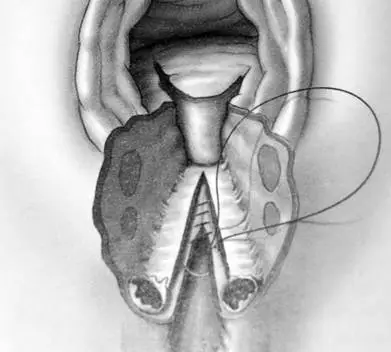

37 歲孕婦,G1P0 ,妊娠 39 週,生產後如圖所示:下列四者中最可能的診斷為何?

本題考核會陰裂傷(perineal laceration)的分級分類,要求考生根據生產後的臨床影像判斷裂傷程度。核心概念為四級會陰裂傷的解剖定義,尤其需掌握各級裂傷所涉及的組織層次,以區分第三度(僅影響肛門括約肌)與第四度(延伸至直腸黏膜)裂傷。

影像分析:

圖片為一張黑白解剖插圖,呈現女性生產後的會陰部(perineum)正面觀,顯示嚴重的會陰裂傷:

解剖結構辨識:

- 中央頂部:陰道(vagina)開口,呈現三角形裂開,可見陰道壁

- 中間縱向結構:直腸(rectum)黏膜明顯撕裂並向前翻出,裂口縱向延伸至肛門正上方,可見直腸黏膜(rectal mucosa)的白色管狀結構外露

- 兩側對稱結構(圓形/橢圓形):為外肛門括約肌(external anal sphincter, EAS)的斷端,兩側各有兩至三個橢圓形肌肉斷面,代表 EAS 完全斷裂後收縮回兩側的肌肉束

- 右側標示圈:以圓形輪廓圈出右側外肛門括約肌的斷端,強調其辨認

- 整體形態:會陰體(perineal body)完全毀損,裂傷上自陰道後壁延伸、下至肛門口,形成菱形大面積傷口

判讀結論:本圖同時顯示(1)外肛門括約肌斷裂(bilateral EAS disruption)及(2)直腸黏膜外露(rectal mucosa e